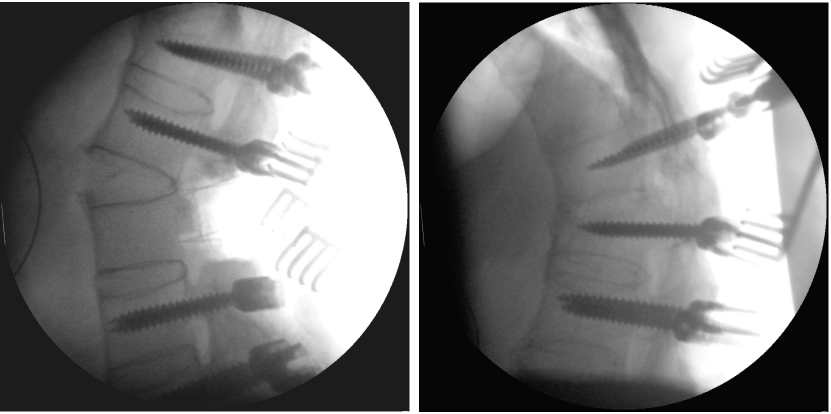

The first part of surgery was performed without any particularity. Screws were inserted and we started with the posterior part of the osteotomy. During this procedure, a change in the position of the spine (increase of lordosis) was observed. The immediately performed fluoroscopy showed a spontaneous fracture at the level of the ankylosed disc L2/3 (Figure 3 [Fig. 3]). It was a wedge-shaped fracture, fortunately without any rotation or translation. The resulting condition could be described as a Smith-Peterson osteotomy. Therefore, we decided not to carry out the initially planned osteotomy at level L3 but rather use the gap from the spontaneous fracture for correction. Thus, additional screws were inserted at the level of L3 and posterior instrumentation was completed. Furthermore, bone was replaced posteriorly to support fusion and surgery could be completed (Figure 4 [Fig. 4]). Postoperatively, we monitored the hemoglobin value and did repeated ultrasound examinations of the abdomen to exclude an impairment of the vessels in front of the lumbar spine.

Figure 3: The intraoperatively taken fluoroscopy shows a fracture of the ankylosed disc L2/3 with a wedge-shaped gape without any translation or rotation (left). The fluoroscopic control performed a short time before to assess the right screw position shows the later fractured level without any particularity (right).

Figure 4: The conventional X-rays of the lumbar spine after the first operation in two planes (ap view left, lateral view right) show the improved position of the spine, however, compared to the intraoperative fluoroscopy (Figure 3), a partial loss of correction.